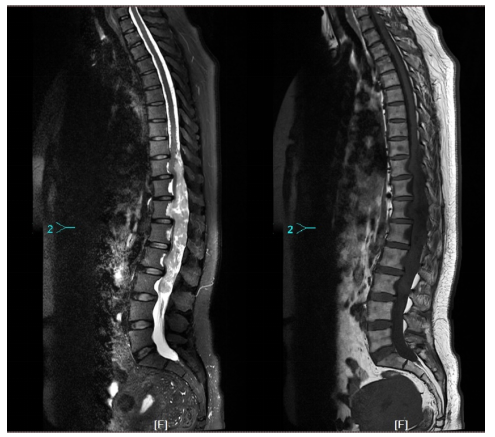

病例1 女性 43岁

患者以“腰部不适1月余”为主诉入院,专科查体双下肢各肌群肌力Ⅳ级,无明显病理征。

结合患者影像学资料,病变部位较长,椎体慢性受压改变,患者症状较轻,考虑病程较长,倾向于良性病变可能;T1等信号,T2混杂信号,局部脊髓信号增粗,髓内肿瘤可能,倾向于室管膜瘤。

行椎管内肿瘤切除+椎板回植术,术后患者下肢肌力正常,术前不适症状明显改善。